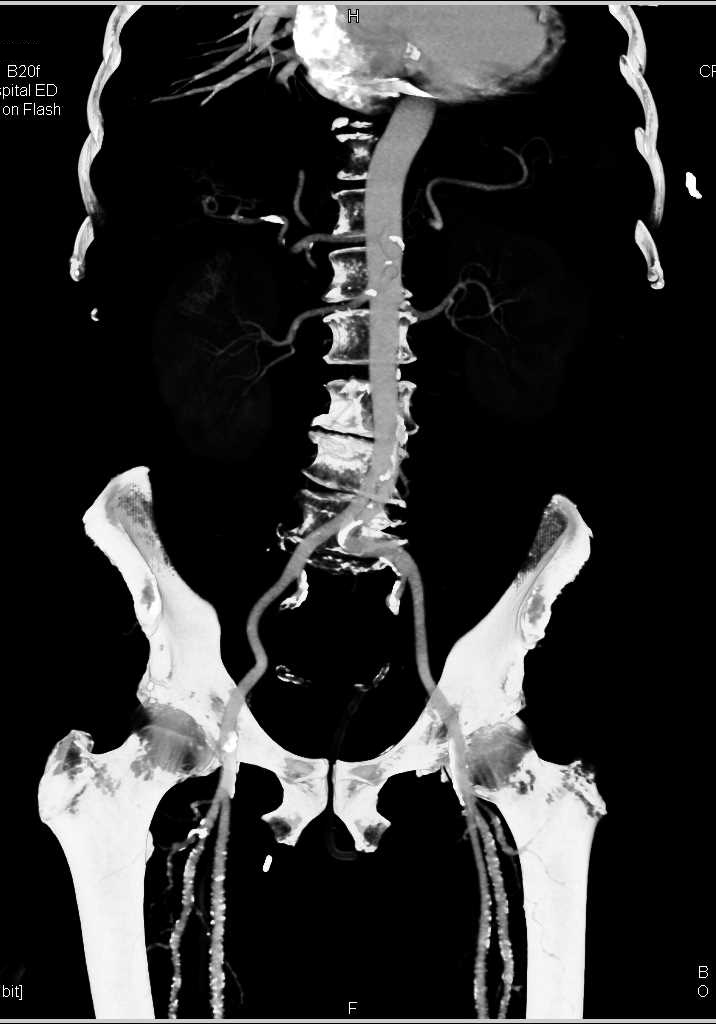

Unusual Clot in Abdominal Aorta and a Site for Emboli